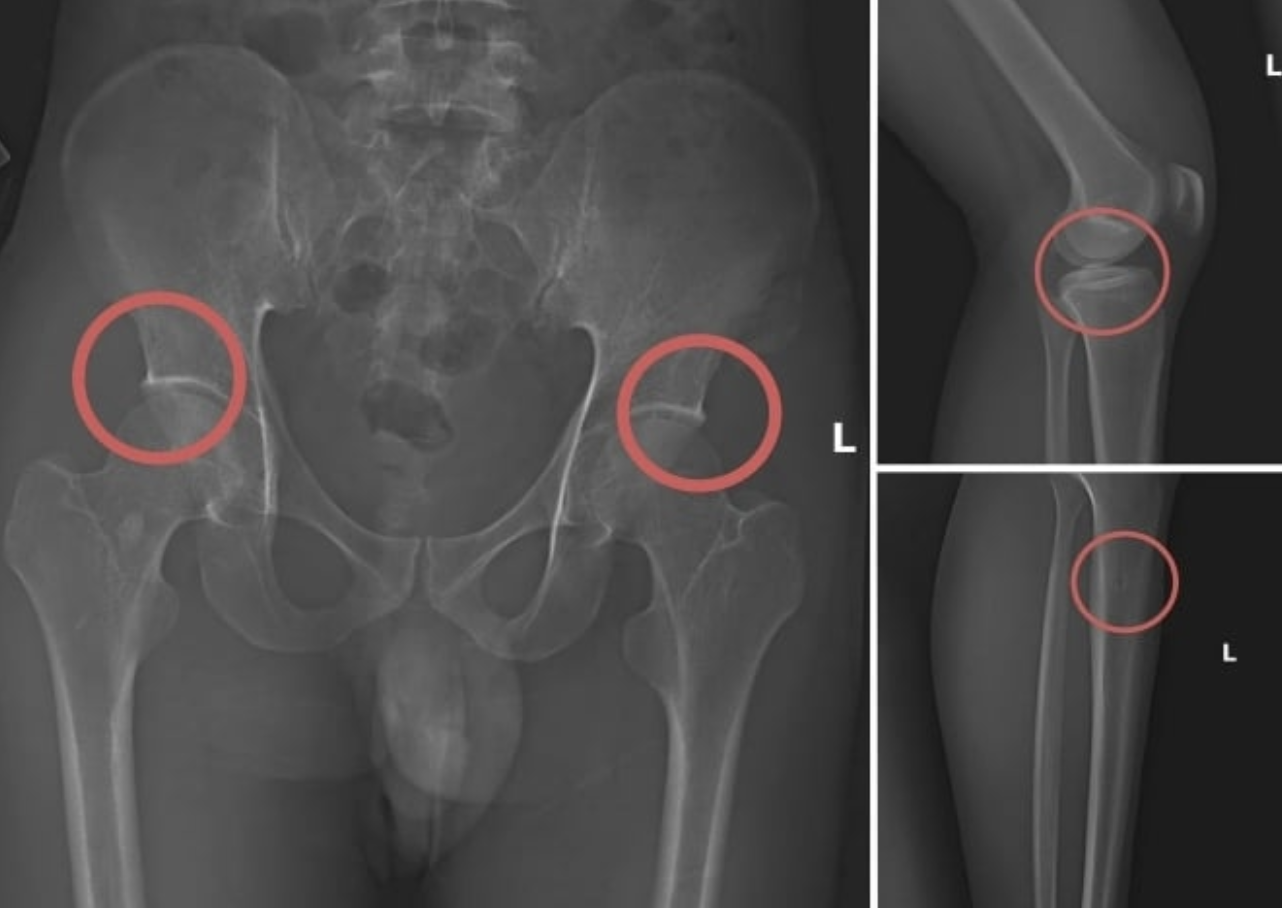

Old  Default Vụ tự đục gãy xương để chiếm đoạt hơn 6 tỷ đồng tiền bảo hiểm: Bác sĩ thốt lên "quá tàn nhẫn”

Liên quan tới vụ việc các đối tượng dùng kim tiêm, búa, đinh để tác động vào xương người mua bảo hiểm, tạo ra các vết nứt, gãy xương giả nhằm chiếm đoạt tiền từ các công ty bảo hiểm, bác sĩ Nguyễn Dương Nhật Thi, Bệnh viện Hữu nghị Việt Đức đã phải thốt lên: “Quá tàn nhẫn”.

Trước đó, vụ án được cơ quan điều tra phát hiện sau khi tiến hành thu thập tài liệu liên quan. Tạ Minh Châu (30 tuổi, cựu cán bộ Trung tâm Y tế huyện Cẩm Khê – Phú Thọ) được xác định là chủ mưu, kẻ cầm đầu. Châu lợi dụng kinh nghiệm lâu năm trong ngành y, am hiểu cấu tạo xương và cơ chế chi trả bảo hiểm đối với thương tích gãy xương nên đã dựng lên một quy trình trục lợi bảo hiểm bài bản.

Đường dây này được tổ chức từ việc vận động người dân mua bảo hiểm, gây thương tích nhân tạo, cho đến hợp thức hồ sơ bệnh án để chiếm đoạt tiền. Khi thương tích đã được tạo ra, Châu cùng đồng phạm dựng hiện trường giả, từ điện giật đến trượt chân ngã suối, nhằm hợp pháp hóa hồ sơ yêu cầu chi trả.